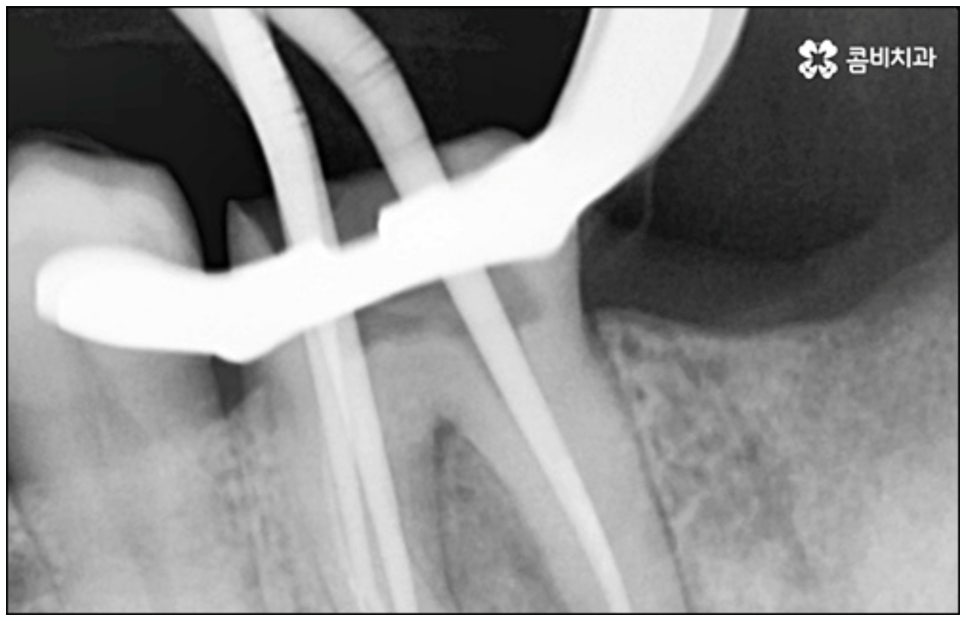

하지만 근래 치의학이 점점 더 발달하고 임플란트 관련 기술이 진일보하면서, 발치한 당일 인공치근을 심고 임시 치아까지 장착하여 바로 씹을 수 있도록 한 당일임플란트 방법이 개발되어 전체 치료 기간을 대폭 줄일 수 있는 가능성이 높아지면서 이에 대한 문의가 많아지고 있어요. 과거에는 보통 발치 후 2~3개월 정도 기다려서 잇몸뼈가 어느 정도 회복된 다음 잇몸을 절개하고 임플란트를 식립하는 방식으로 진행을 했었다면 당일임플란트 방식은 인공 치근 주변 남는 빈 공간을 뼈이식술을 통해 바로 보강, 이후 잇몸뼈가 자연스럽게 아무는 과정에서 좀 더 빠르게 골융합이 이루어지도록 돕기 때문에 일반 임플란트 방식에 비해 기간을 단축시켜 줄 수 있는 거예요.

또한 한 번 식립된 인공 치근이 뼈조직과 골융합되고 난 다음에는 그 위치와 방향을 수정하기 어려운 만큼 혹시 모를 부작용이나 재수술 위험 없이 임플란트 치아를 사용할 수 있도록 안정성이 검증된 정품 재료를 사용하고 있는지, 잇몸 상태와 구강 구조를 세밀하게 체크할 수 있는 3D CT와 같은 정밀 검진 장비를 활용하는지 등등을 함께 꼼꼼하게 체크해 볼 필요가 있어요. 그리고 언급했던 것처럼 사후 관리 역시 임플란트 수명에 큰 영향을 주니 철저한 케어 시스템을 갖추고 임플란트 유지 관리를 도와주는 치과에서 진행하는 것 역시 중요하다고 할 수 있습니다.